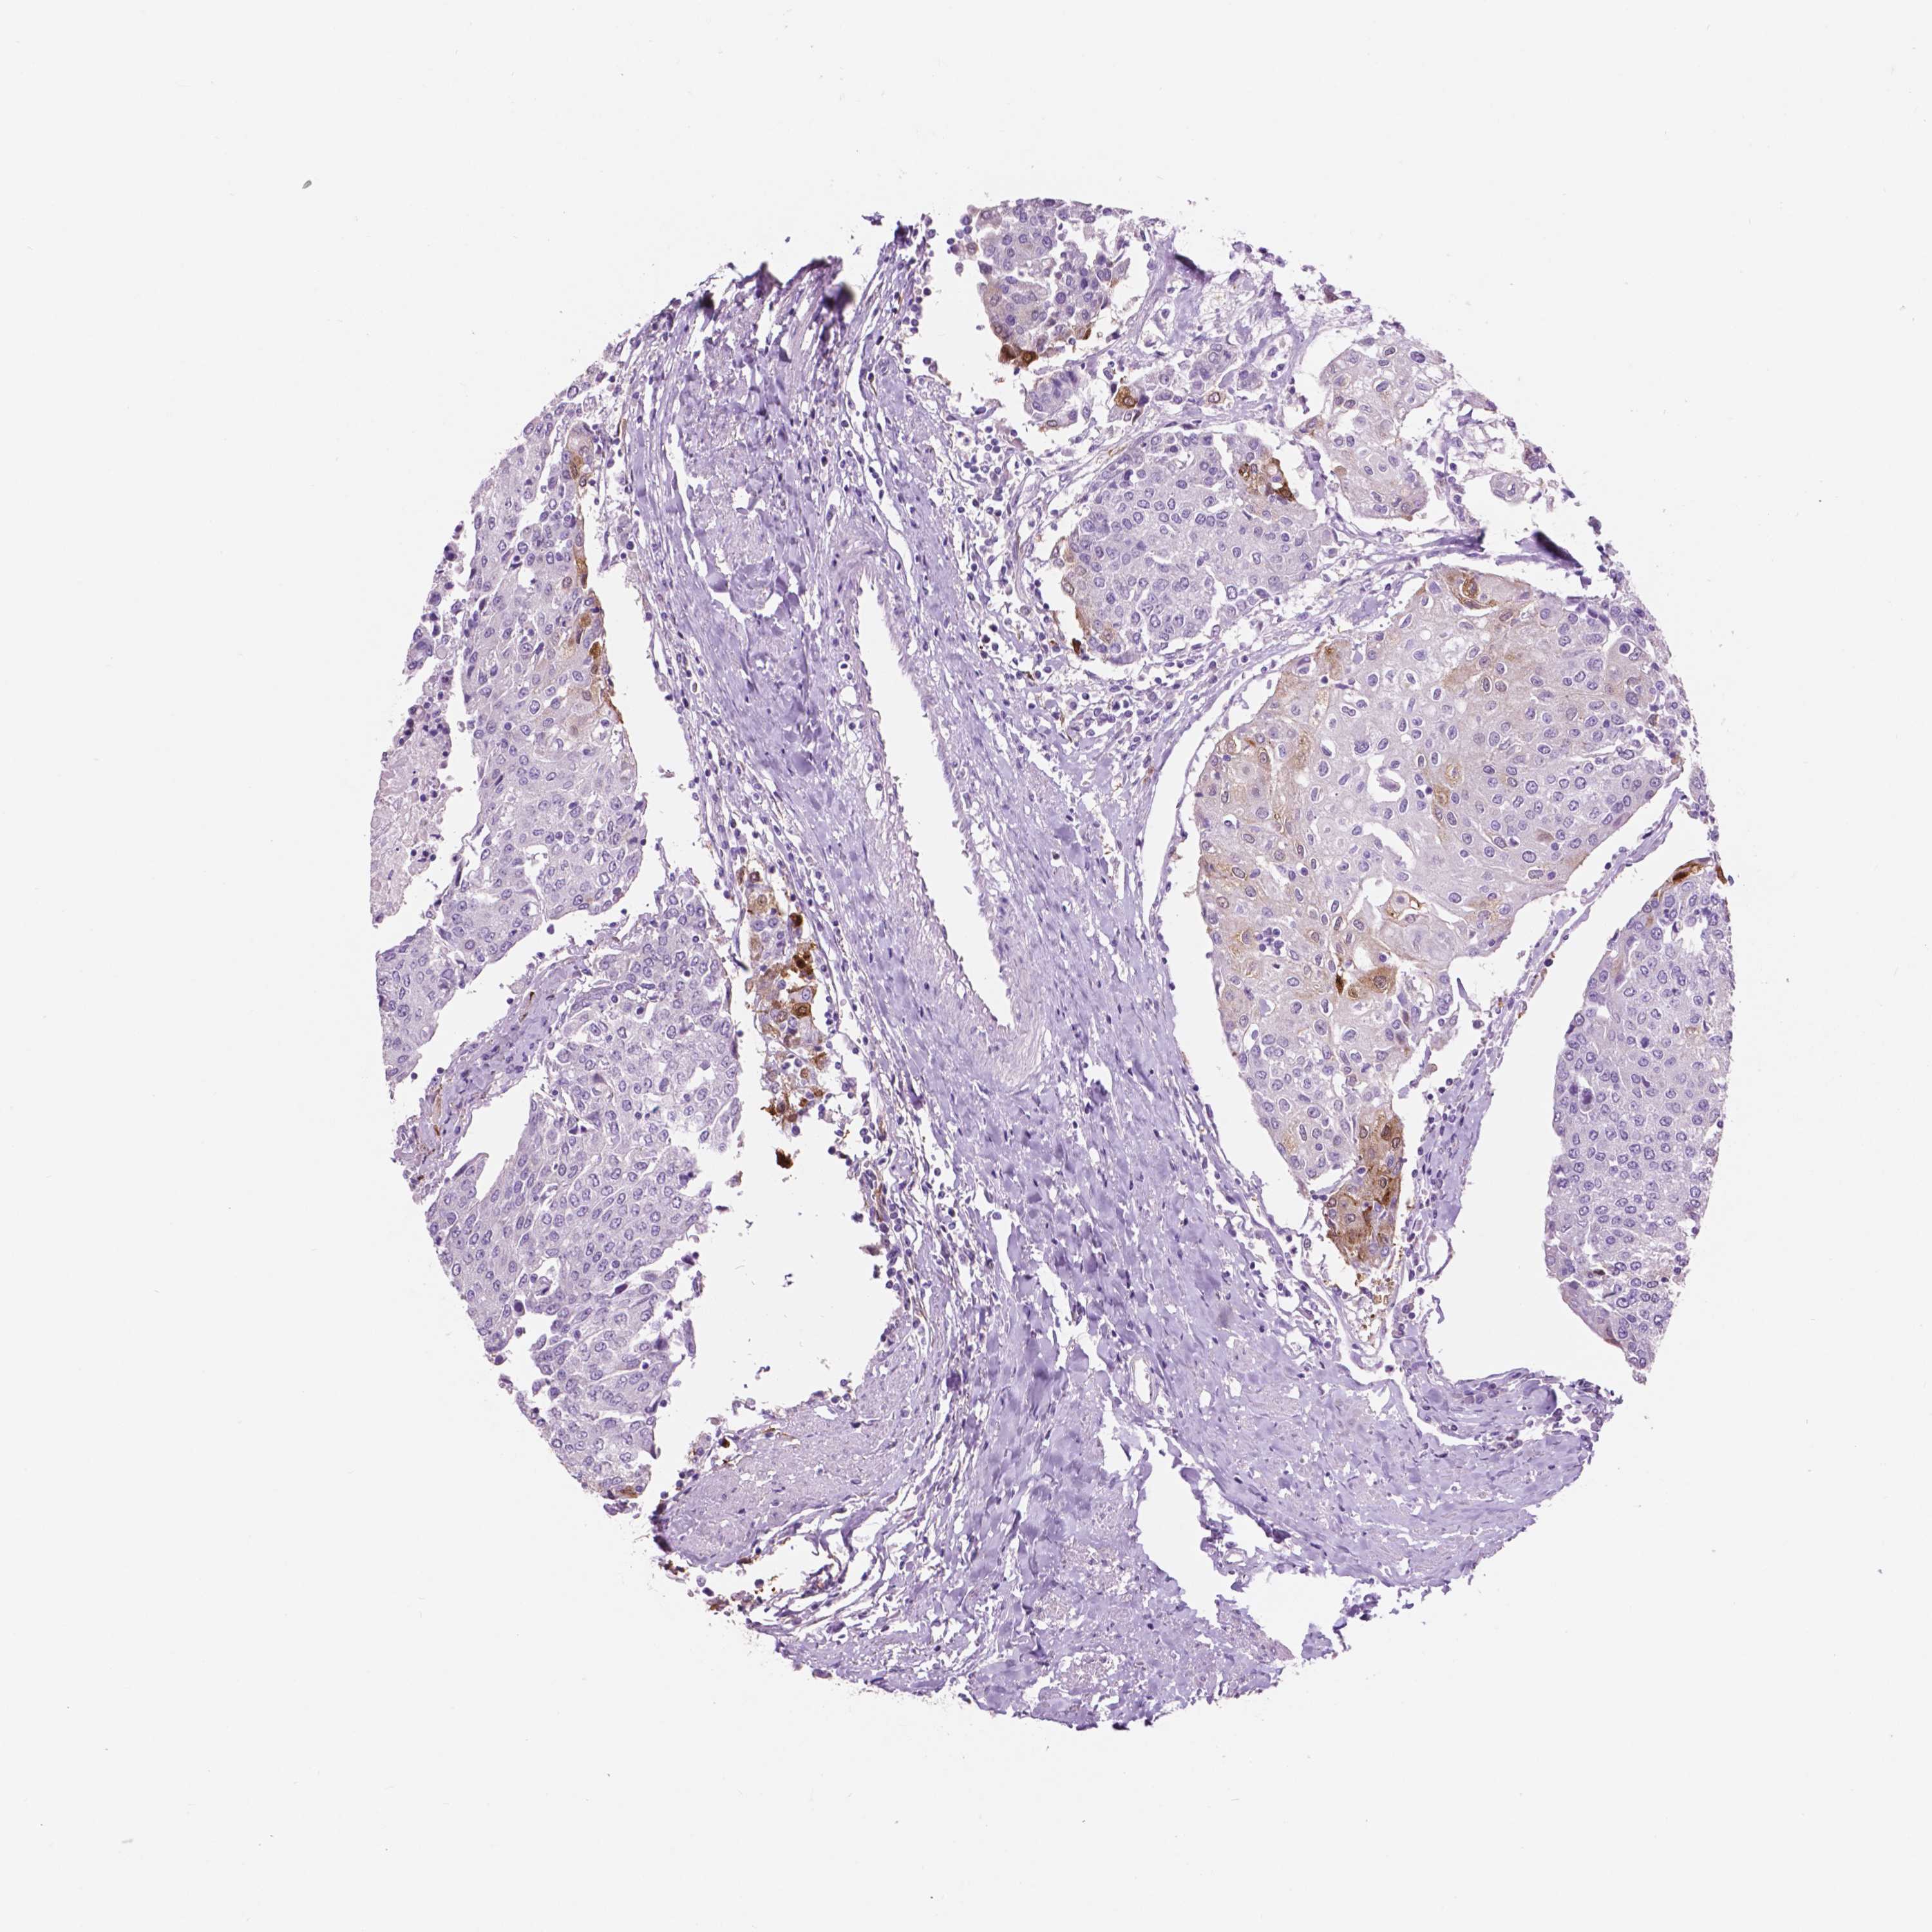

UROTHELIAL CANCER - Protein expressioni

A mouse-over function shows sample information and annotation data. Click on an image to view it in a full screen mode. Samples can be filtered based on level of antibody staining by selecting one or several of the following categories: high, medium, low and not detected. The assay and annotation is described here.

Note that samples used for immunohistochemistry by the Human Protein Atlas do not correspond to samples in the TCGA dataset.

Antibody stainingi

Antibody staining in the annotated cell types in the current human tissue is reported as not detected, low, medium, or high, based on conventional immunohistochemistry profiling in selected tissues. This score is based on the combination of the staining intensity and fraction of stained cells.

Each image is clickable and will lead to virtual microscopy that enables deeper exploration of all samples and also displays staining intensity scores, fraction scores and subcellular localization as well as patient and tissue information for each sample.

Antibody HPA023072

Antibody HPA023149

Antibody HPA027772

Antibody CAB072820

Staining

High

Medium

Low

Not detected

Intensity

Strong

Moderate

Weak

Negative

Quantity

>75%

75%-25%

<25%

None

Location

Nuclear

Cytoplasmic/membranous

Cytoplasmic/membranous,nuclear

Urothelial carcinoma, Low grade

Urothelial carcinoma, High grade